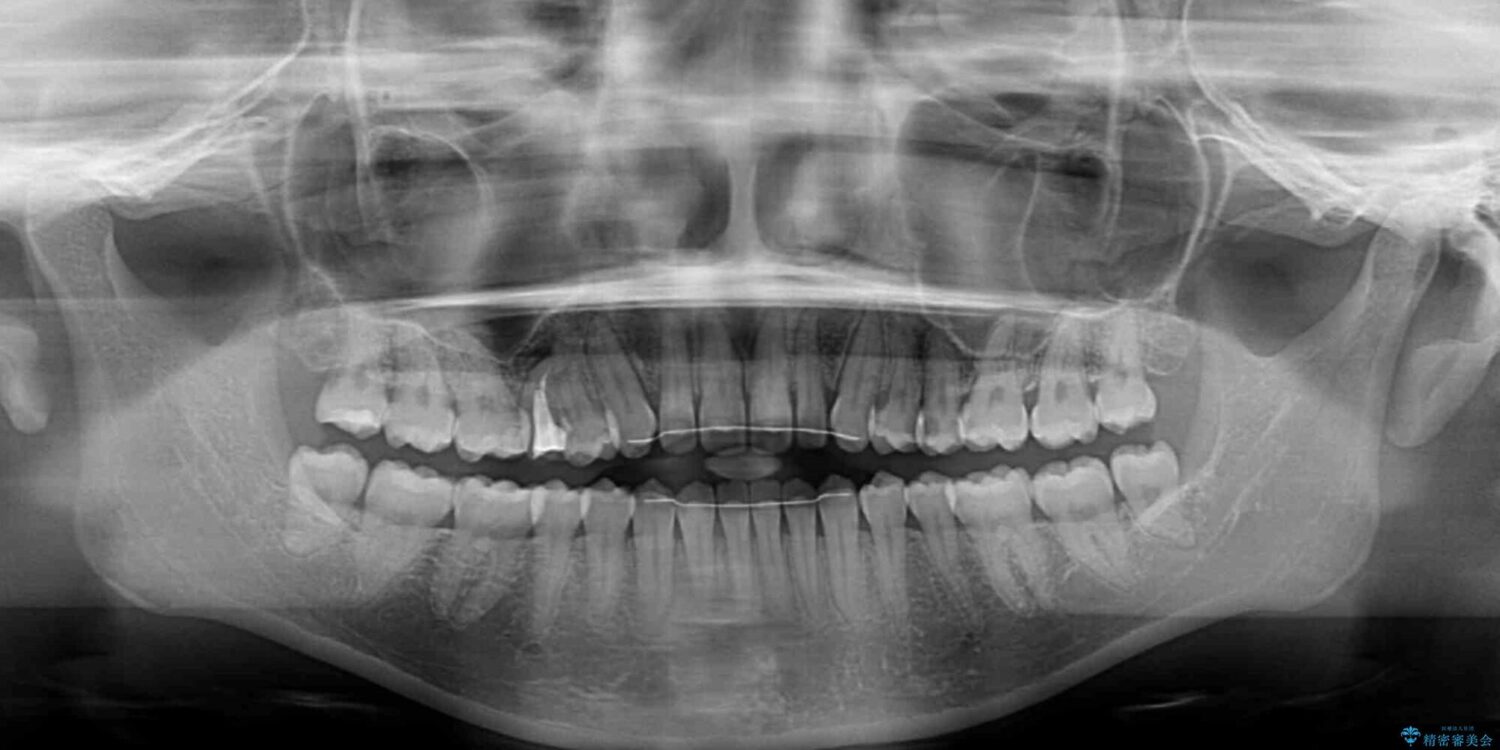

前歯の上下スペースと前歯の隙間を気にして来院された患者様です。

飲み込みや話をするときに舌を突出させる癖が強くあり、それが原因でスペースが空いていました。

舌癖を改善するためのトレーニングを行いながら、インビザラインにより上下の前歯の隙間を閉じていくこととしました。

治療前

• 隙間だらけの歯列 インビザラインで改善 治療前画像